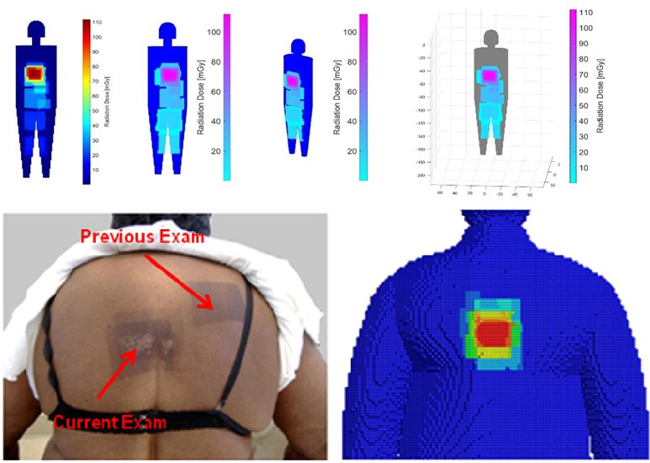

- Real time dose monitoring of patients

c) Low dose imaging

- ALADA (as low as diagnostically acceptable)- dose management of CT-guided interventions of the lumbar spine

- Prediction of ALADA Doses for Implant Site Analysis Using Slope of Hounsfield Units- external collaboration with King Saud University

- Development of an ALADA reference quality approach in craniofacial trauma CT

- Clinical verification of an ALADA protocol in craniofacial trauma